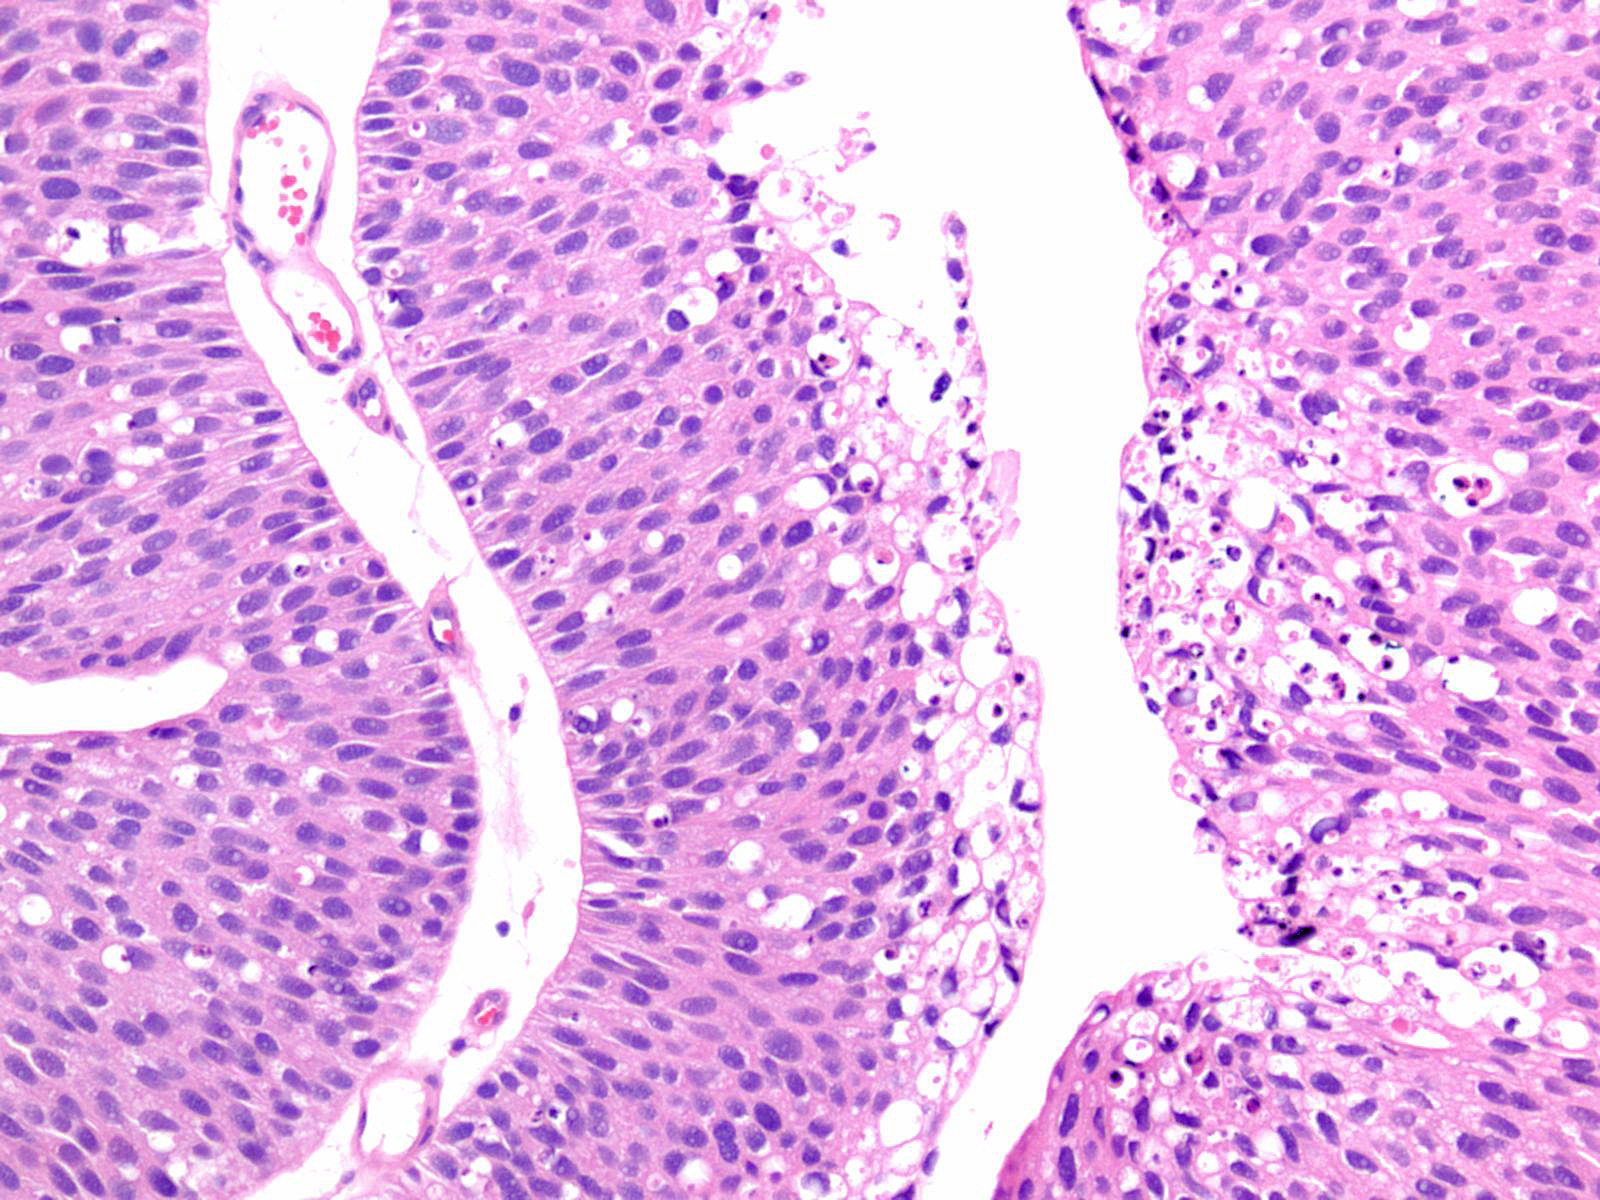

Bladder Papillary Lesions

Case ID: 212